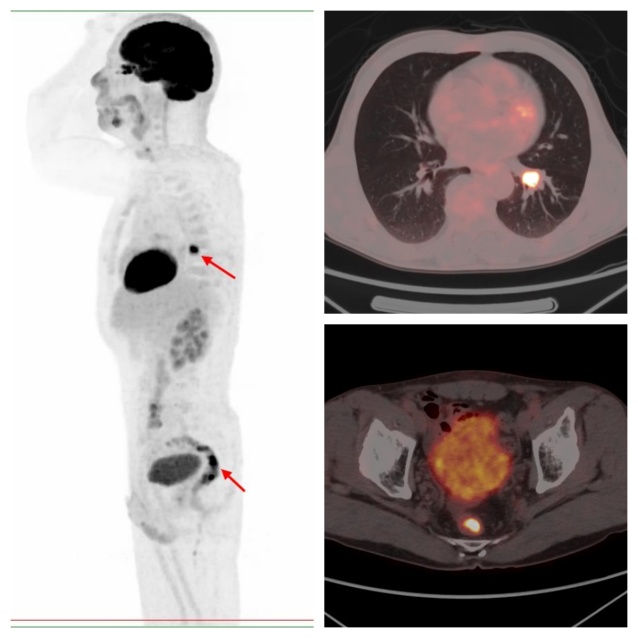

病例2,PET/CT示左肺下葉、直腸代謝異常,符合雙原發(fā)癌;之后患者行支氣管鏡下活檢,病理證實(shí)原發(fā)肺鱗癌;行腸鏡下活檢,病理證實(shí)為原發(fā)直腸潰瘍型腺癌。